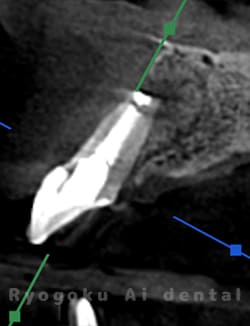

Case14

-

術後半年レントゲン

- 原因

- 左上1、2番歯根嚢胞

- 治療内容

- 歯根端切除法

- 治療費用

- ¥77,000×2

前歯の違和感が治らず、他院では治療を断られたとのことでご来院された患者様です。左上1、2番に口蓋側まで及ぶ嚢胞が存在したため、歯根端切除術を行いました。経過良好です。